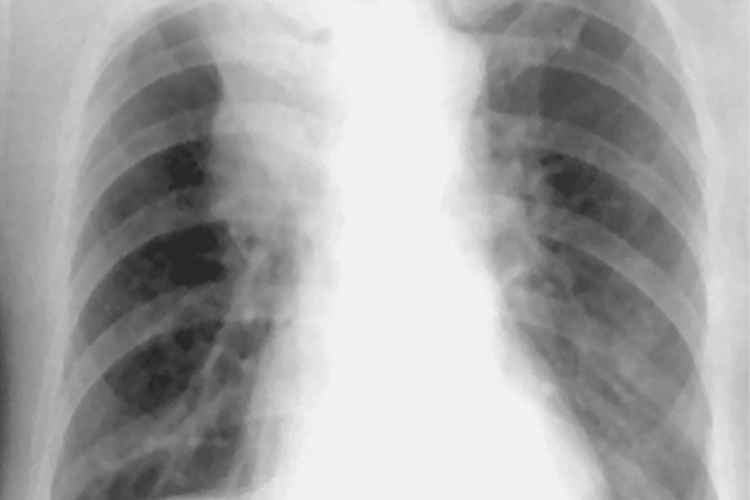

中央型肺癌

中央型肺癌早期胸片上常无异常表现,偶尔可有局限性肺气肿或阻塞性肺炎表现。中晚期胸片上主要表现为肺门区肿块,呈分叶状或边缘不规则形,常可伴有阻塞性肺炎或肺不张。